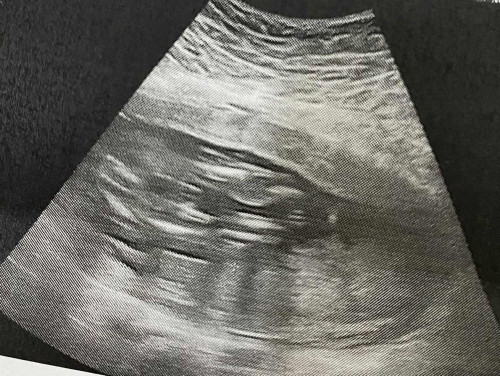

แม่ ๆ พอมองออกไหมคะว่าเป็นหญิงหรือชาย พอดีคุณหมอบอกอาจจะเป็นผู้หญิงค่ะ เลือกซื้อชุดไม่ถูกเลยค่ะ

เชื่อหมอค่ะ แต่ถ้ามีคำว่าอาจจะ ให้คุณแม่ซื้อของสีกลางๆไว้ค่ะ บางทีเพศน้องก็ไม่ตรงกับที่หมอบอกแบบชัวร์ๆ